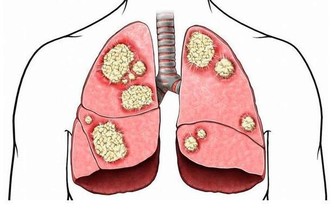

一般來說,健康的標誌就是你感受不到其存在。比如不感冒的時候,你就意識不到呼吸順暢多重要;

不咳嗽的時候,你就不知道肺出問題多難受;